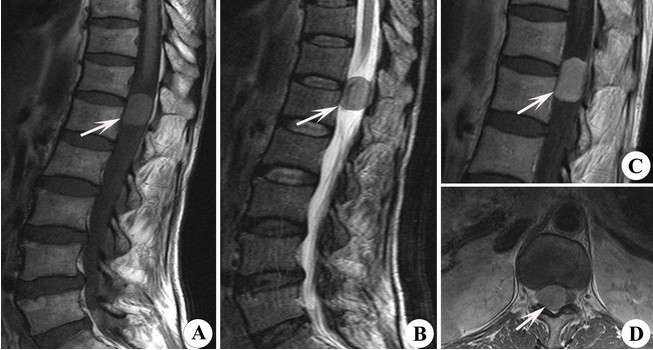

髓内脊髓肿瘤(IMSCTs),如下图所示,是指硬膜内 脊髓肿瘤 的一个亚群,由脊髓内的细胞产生,与相邻结构如神经根或脑膜相对。它们比脑瘤少见得多,据认为占中枢神经系统全部固有肿...

椎管内肿瘤,也称 脊髓肿瘤 ,包括生长于脊髓、神经根、脊膜和椎管壁组织的原发和继发性肿瘤,约占原发性中枢神经系统肿瘤的15%。 椎管内肿瘤的症状和体征在疾病早期常常为隐匿性...